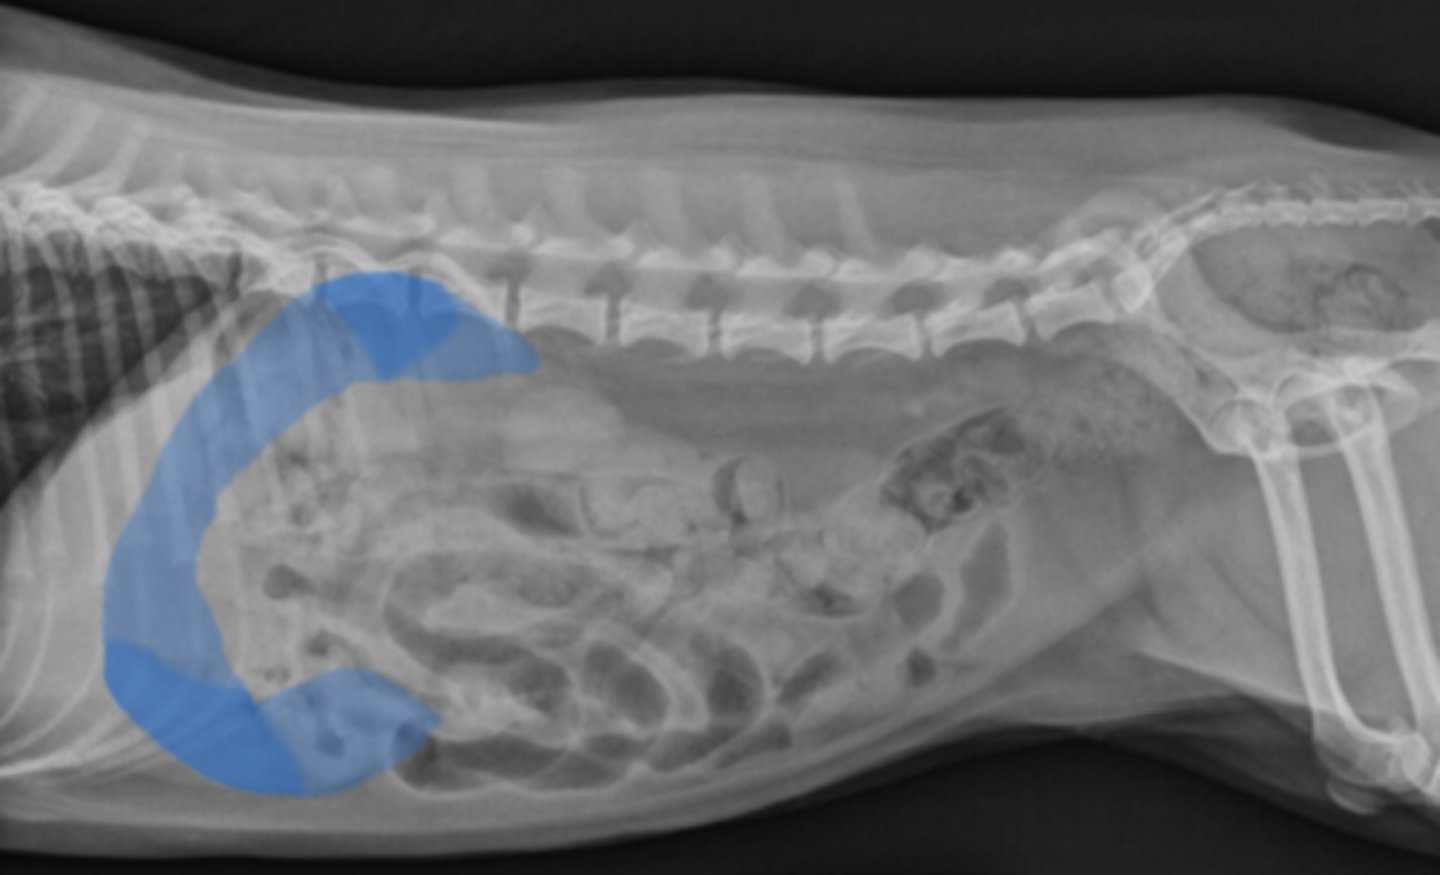

Linear foreign body

Dx of cat vomiting;